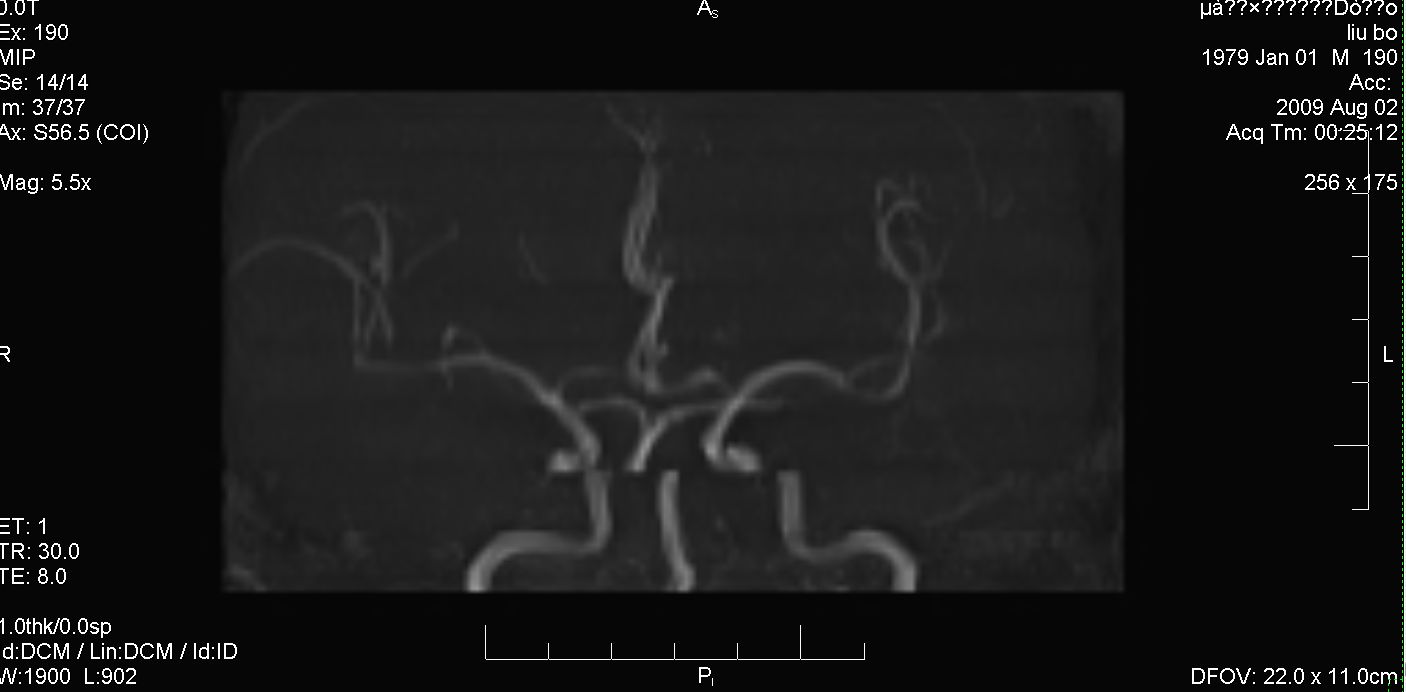

标题: MRI2379:30岁,男,癫痫10年,请各位看一下;CT示:左颞叶钙 [打印本页]

考虑左侧颞叶脑血管畸形(avm)。----t1低等高混杂信号,t2等高信号周边较多流空血管影[冠状位明显],mra左侧大脑中动脉受压,远侧聚集.